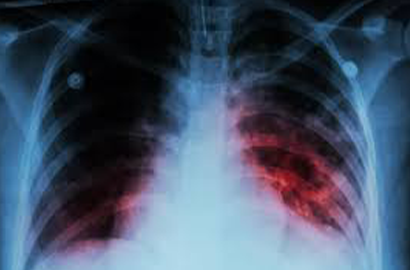

• Chest X-ray: To visualize lung abnormalities that may indicate TB infection.